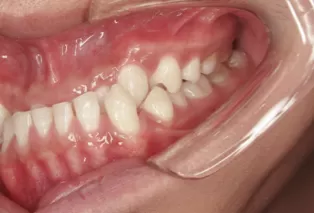

Photos intra-orales après traitement